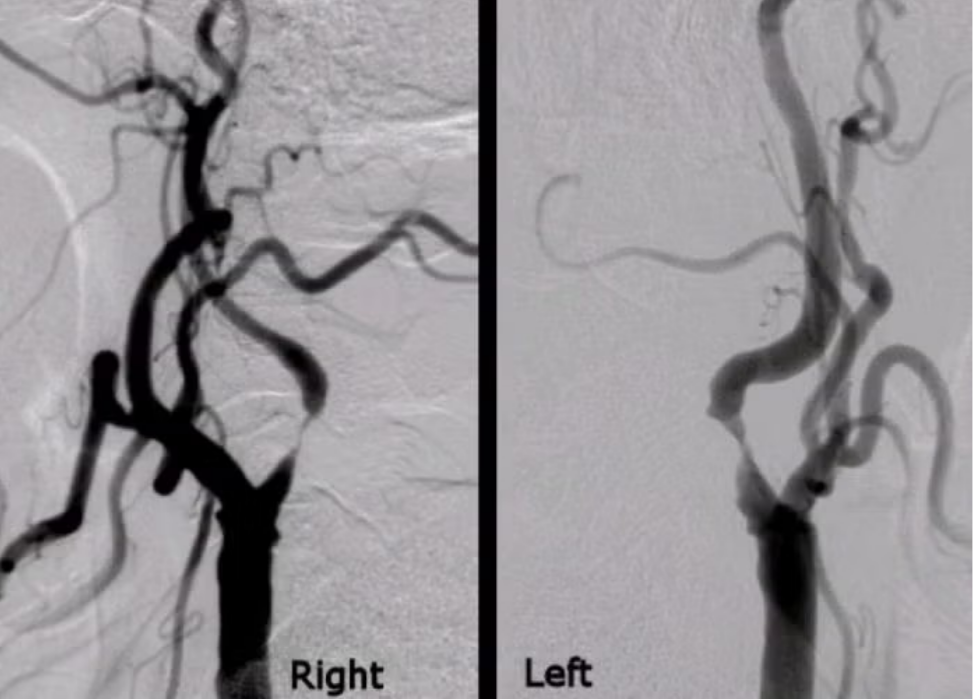

A thin catheter is inserted through an artery in the wrist or groin and guided to the narrowed carotid artery under real-time imaging (angiography).